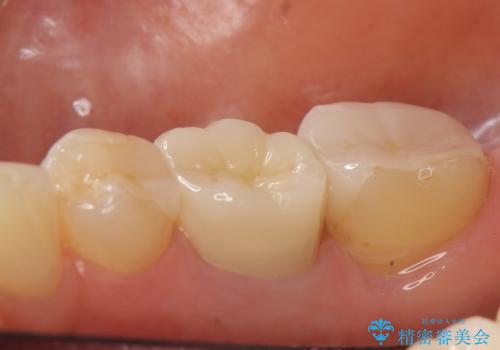

右上の567ブリッジを外したところ、右上5は歯根破折により保存不可能だったため、右上56部にインプラントを埋入し欠損補綴を行いました。

今回用いたオールセラミッククラウンはジルコニアフレームという白い素材の上にセラミックを盛っているため、審美性が非常に高いのが特徴です。

また、ジルコニアは人工ダイヤモンドの材料にも使われているほど高い強度を持っており、そのためオールセラミッククラウンは審美性だけでなく、奥歯やブリッジの補綴も可能とするクラウンです。